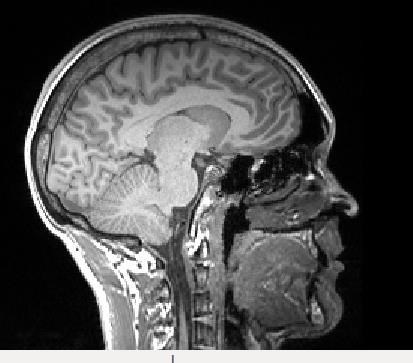

Ja. Här är förresten en T1-viktad (T1w) MR-bild på min hjärna.

Vad coolt. På din hjärna? Hur fick du tag på den bilden?

detrr skrev :Vad coolt. På din hjärna? Hur fick du tag på den bilden?

Mm :)!

Jag sommarjobbade på Karolinska sjukhuset i somras, på MR-avdelningen. Jag läser ett fysikprogram på Stockholms universitet (har gått 2.5 år av 5) med inriktning mot Sjukhusfysik. Jag har inte läst någon kurs i MR, men lyckades få ett jobb där ändå. Jag efterbearbetade MR-bilder i ett dataprogram.